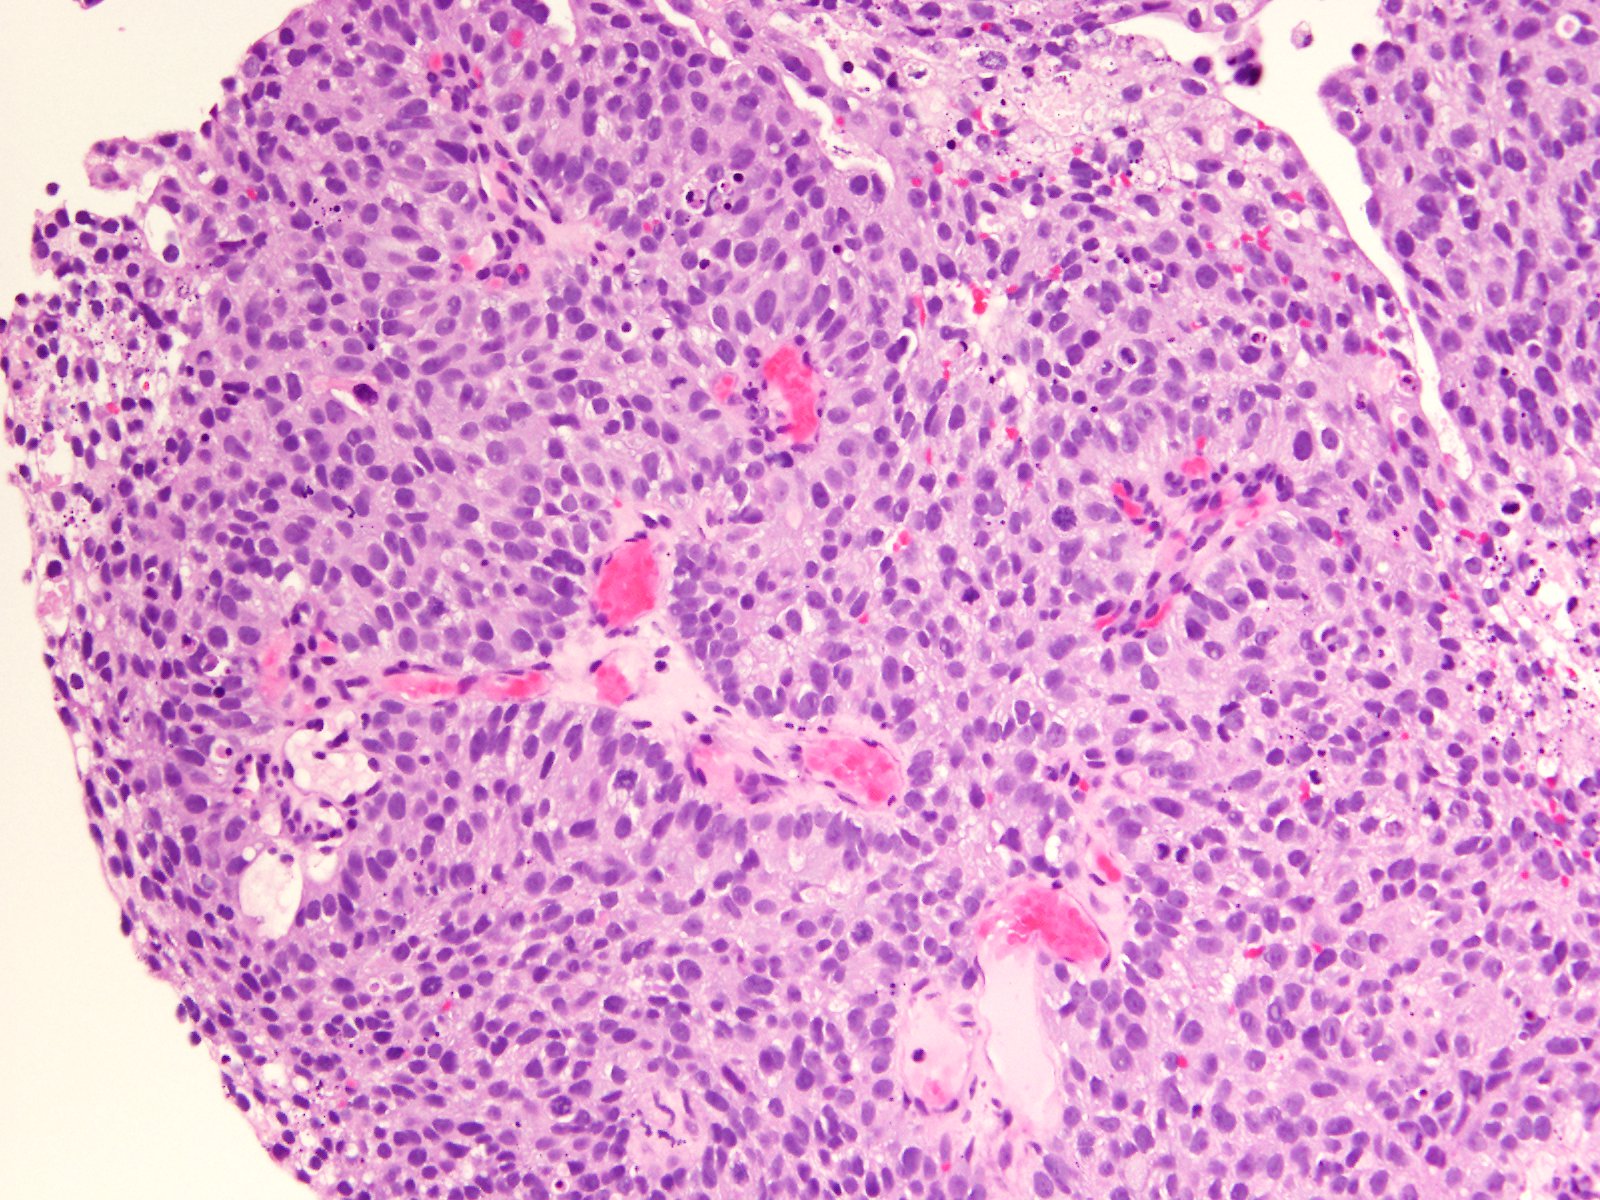

Bladder Papillary Lesions

Case ID: 565